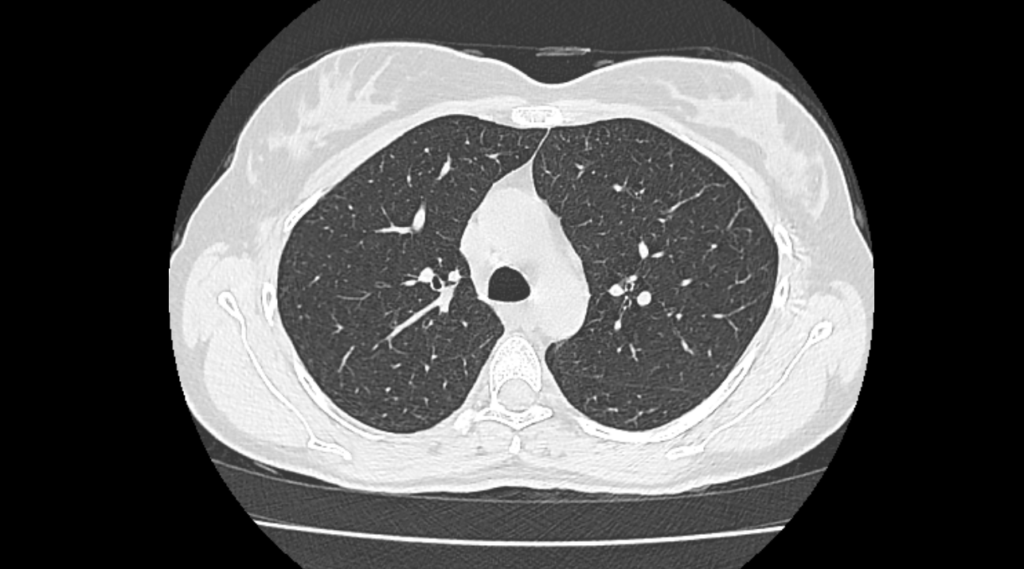

CT Imaging

CT